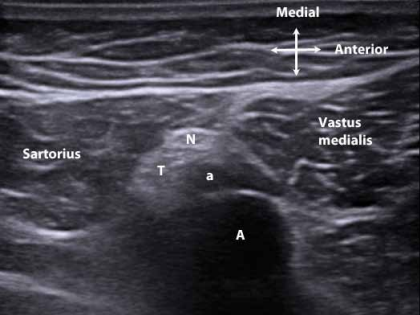

Figure 1. Distal and medial to the adductor canal near the superior-most aspect of the patella. Saphenous nerve (N). Popliteal artery (A) and vein. Saphenous branch of the descending genicular artery (a). Tendon of the adductor magnus muscle (T).

After the saphenous nerve exits the adductor canal, it travels with the saphenous branch of the descending genicular artery just beneath the sartorius muscle from the anterior to the posterior edge of the muscle (Fig 1).[3-5] This occurs where the femoral artery descends through the adductor hiatus into the popliteal fossa. At this point the saphenous nerve crosses over the tendon of the adductor magnus muscle that is interposed between the nerve and femoral artery as the nerve exits the canal (Fig 2).[3]